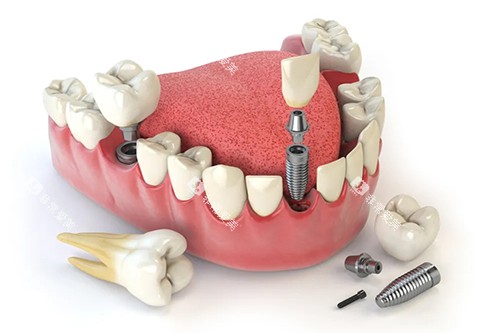

重庆美奥口腔医院涵盖了口腔种植、口腔正畸、牙齿修复、牙齿美白、儿童口腔等多个领域的诊疗项目。

例如,在口腔种植方面,医院采用靠前的种植技术和优质的种植体,为缺失牙患者修复牙齿功能和美观;在口腔正畸方面,提供传统金属矫正、陶瓷矫正、隐形矫正等多种矫正方式,满足不同患者的需求。